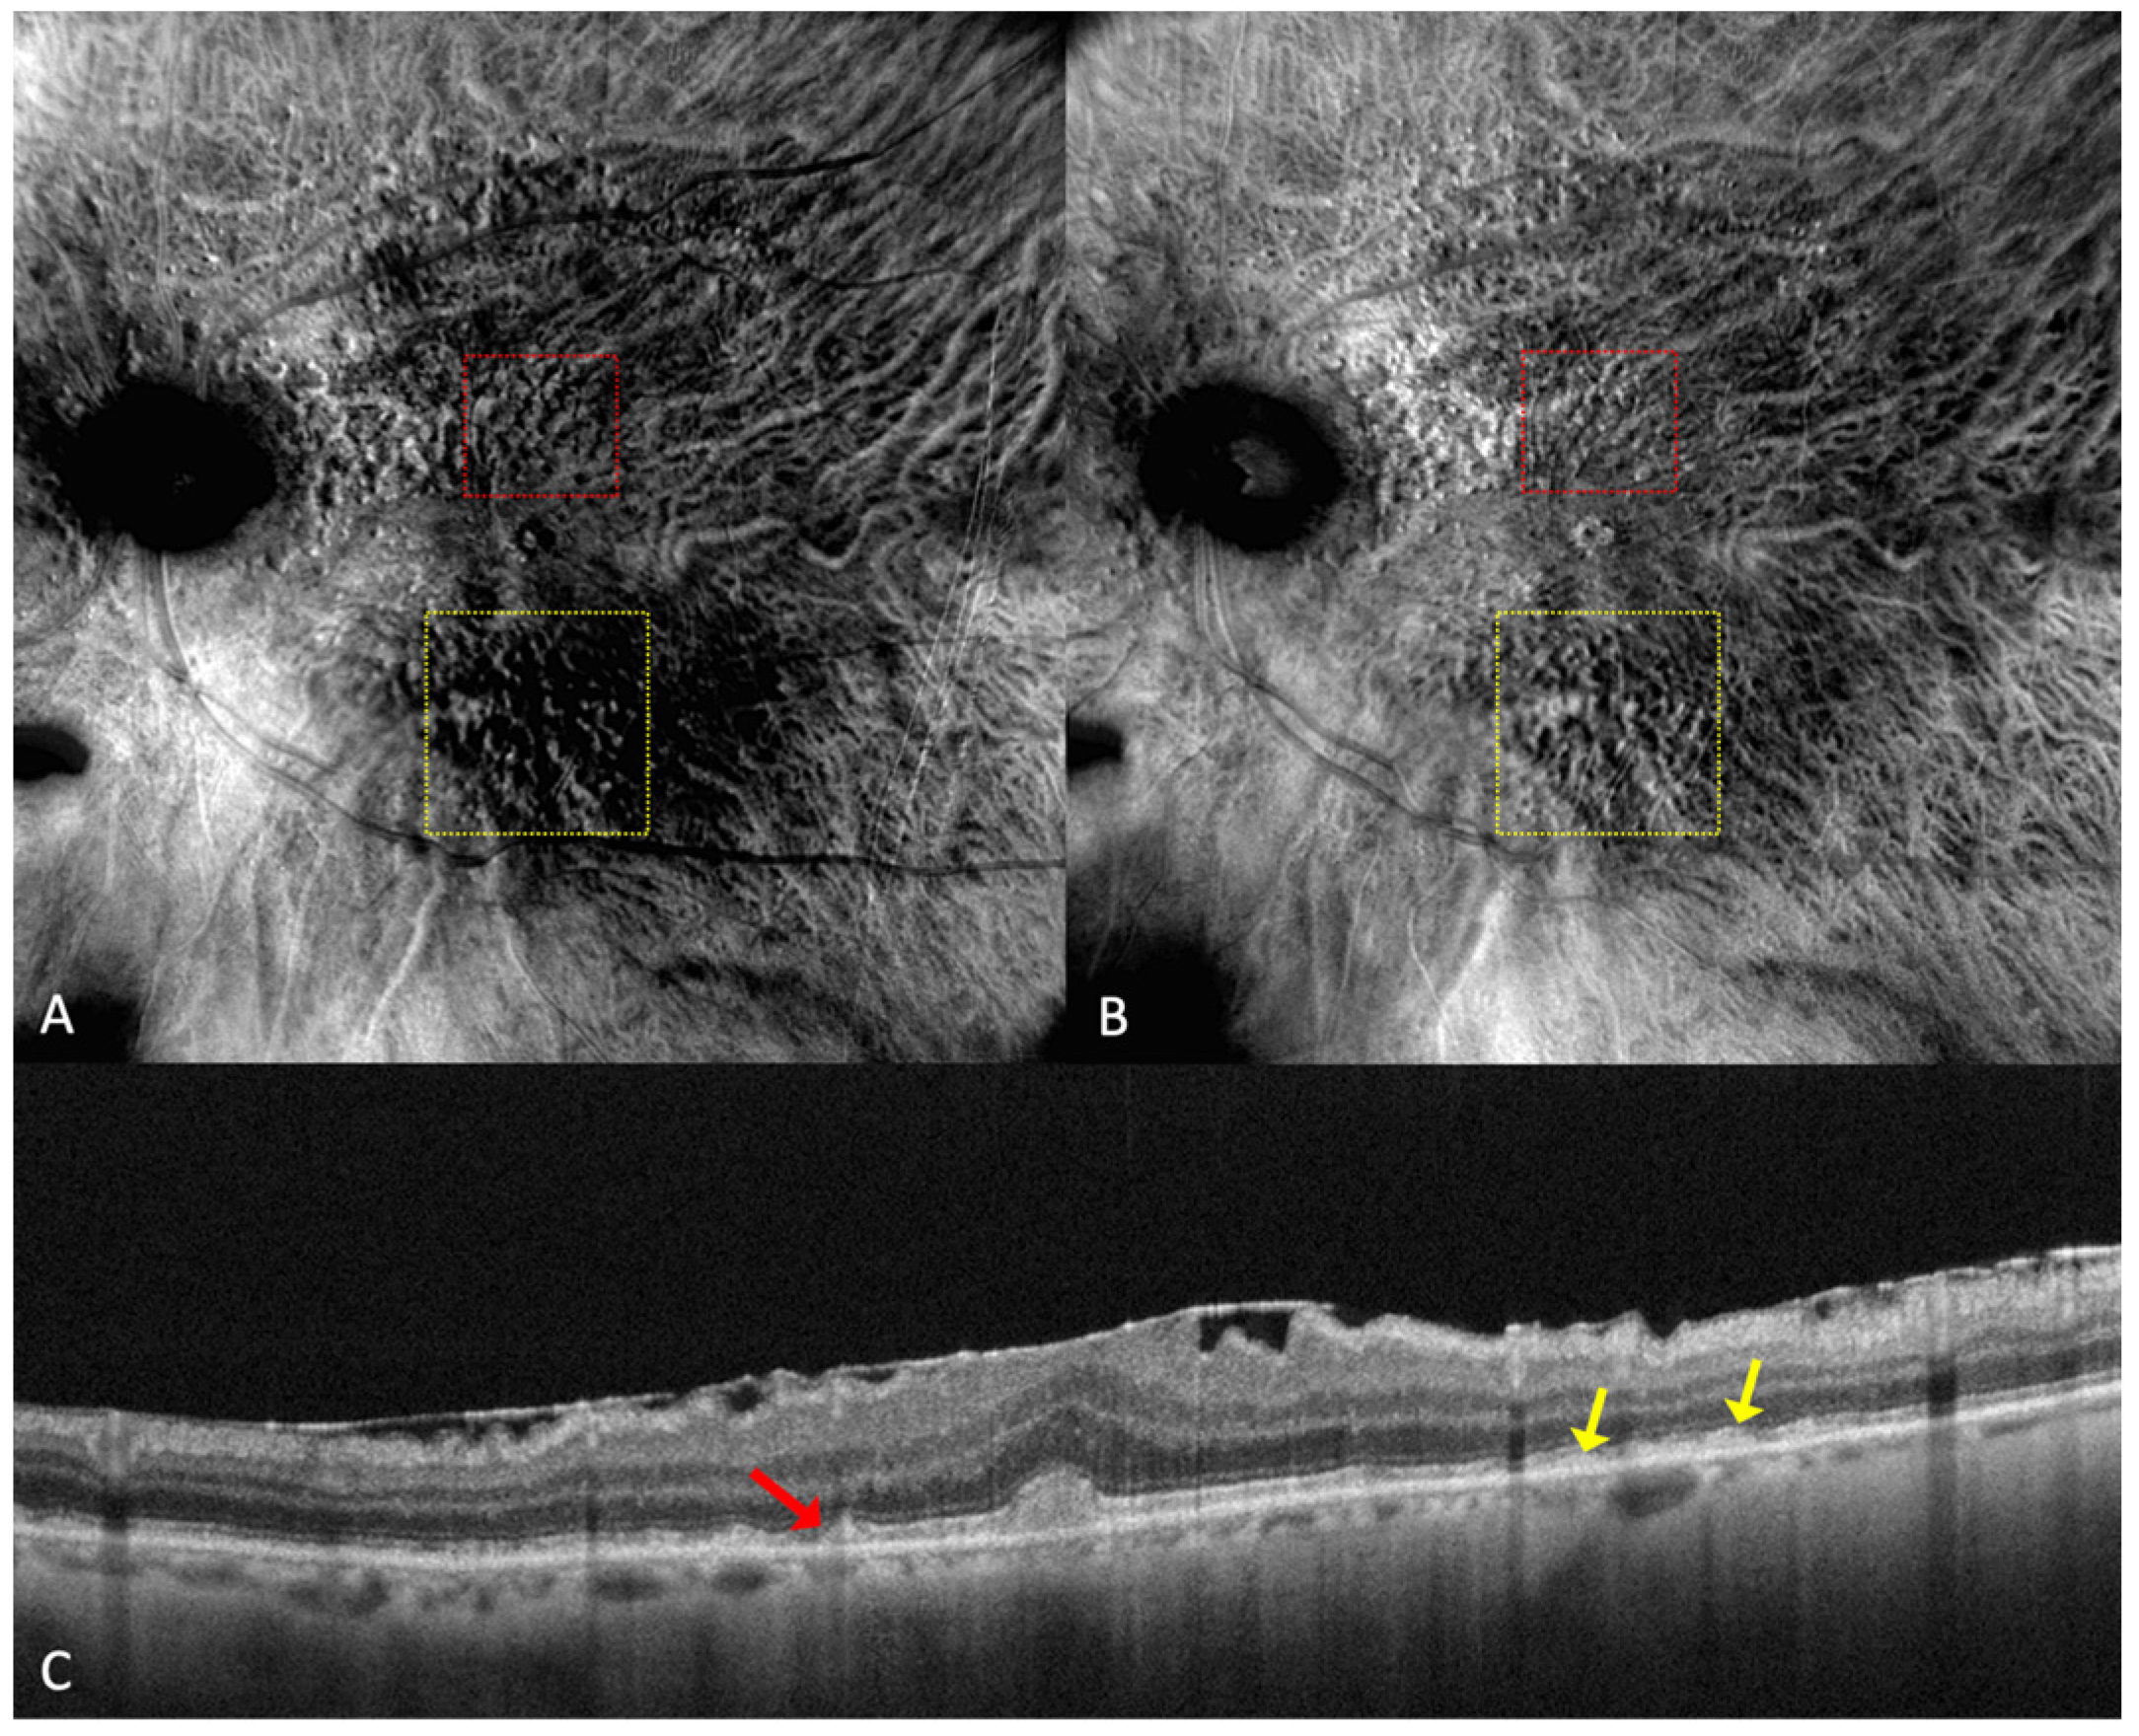

Figure 5.

Drusen and dot subretinal drusenoid deposits (SDD) in a patient with co-existent angioid streaks: (A) cSLO showing multiple drusen and SDDs, with peripapillary radiating irregular lines. (B) In green FAF, temporal to the fovea, drusen are seen as hypo- and hyper-autofluorescent round lesions. (C) In retromode deviated right, elevated lesions can be seen, and in (D) retromode deviated left, small, depressed lesions are detected. (E) En face OCT of (F) SD-OCT shows multiple small, medium, large drusen and also dot SDD (red arrow).